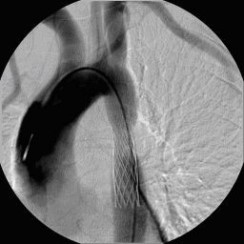

Erfolgreiche Implantation eines transjugulären intrahepatischen portosystemischen Shunts (TIPSS) bei Leberzirrhose und refraktärem Aszites. Darstellung der Lebervenen

(Bild 2 von 4)